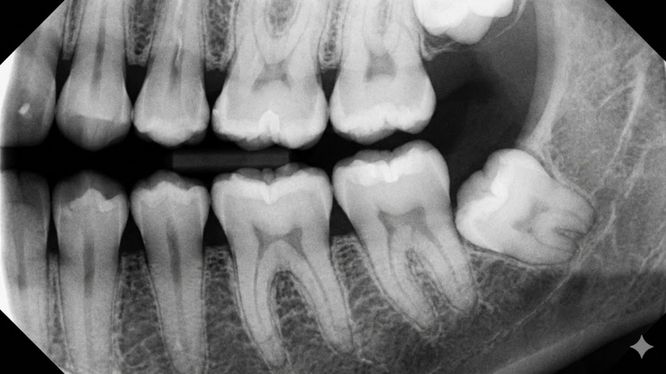

La radiografía dental es un estudio de imagen que permite observar lo que no se ve a simple vista durante una revisión clínica:

- El interior del diente

- Las raíces

- El hueso que sostiene tus piezas dentales

- Zonas ocultas entre dientes

- Áreas profundas bajo la encía

Es decir, nos muestra lo que el espejo no puede 👀🦷.

🦠 Caries ocultas

Especialmente entre dientes o debajo de restauraciones antiguas.

🧬 Infecciones en la raíz

Pueden no doler durante mucho tiempo, pero afectar el hueso.

🦴 Pérdida ósea

Clave para prevenir enfermedades periodontales y movilidad dental.

🦷 Dientes retenidos o mal posicionados

Frecuente en muelas del juicio.

⚠️ Lesiones, quistes o cambios anormales

Que solo son visibles mediante estudios de imagen.